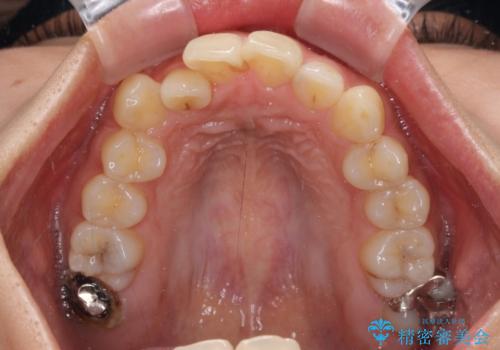

【モニター】歯列が狭くデコボコが気になる 急速拡大装置を用いたインビザライン矯正

- 奥歯の咬み合わせと治療を放置したまま奥歯を気にして来院された患者様です。

上顎骨の幅が下顎骨よりも小さいので、拡大装置により骨幅を広げて上下関係を改善し、その後インビザラインにて歯並びを整えることとしました。

矯正治療後には土台のままとなっている歯をセラミッククラウンにて補綴治療を行うこととしました。

上下の骨幅を改善したことで、スムーズに歯列矯正を行うことができました。

土台のまま放置されていた歯は土台の状態で咬み合っていましたが、急速拡大を行った際に咬み合わせが著しく挙上されたため、その際に土台を大きくすることで咬み合う歯との距離を確保しました。